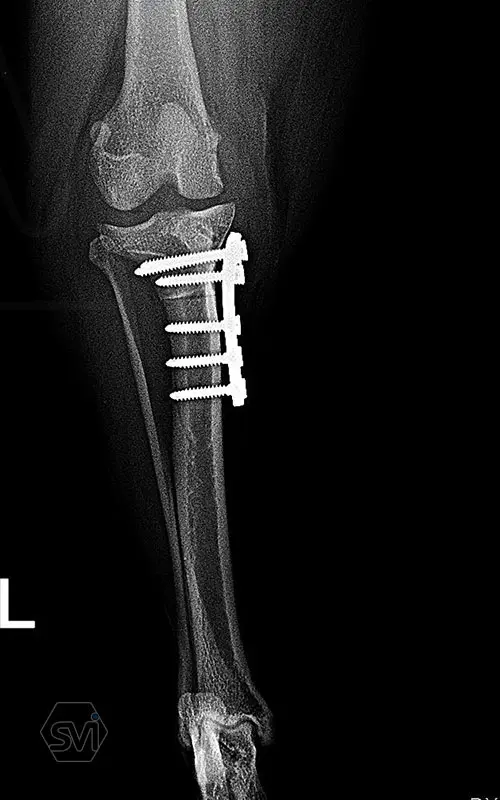

Multifunctional symmetrical long polyaxial locking plate - designed for the treatment of fractures close to joints

A special member of the polyaxial locking plate family is the multifunctional long plate, which is an extended version of the well-known symmetrical TPLO plate, with a 5-3 hole distribution. The plate also received a DCP hole to be able to create compression, and there is a mini-hole on the head end to facilitate the placement of the temporarily used K-nail. The burrs on the side facing the bone surface are intended to reduce the contact surface between the plate and the bone (limited contact).

The plate is a member of the large polyaxial locking family, suitable for 2.7-3.5-4.0 mm screws. We recommend it for fixaton of fractures close to joints, wedge osteotomies with axis correction (closing and opening), or for CWTO operations.